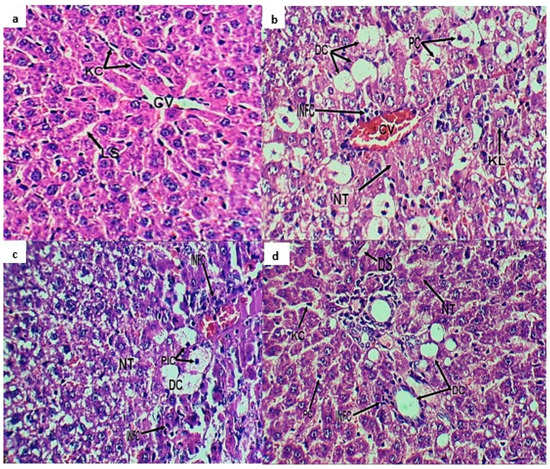

2.3. Histopathological Investigation

4.4.4. Histopathological Investigation